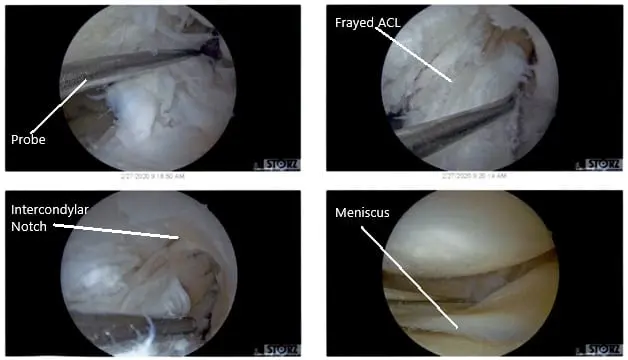

Intraoperative Arthroscopic Views of the left knee.

There were some medial margin tearing and fraying of the lateral meniscus which was taken care of with the shaver and meniscectomy performed to stable margins. The ACL (history of ACL reconstruction) showed fraying in the intertrochlear notch, but the ACL was intact.

Debridement of the ACL was performed. Clean up of the meniscocapsular junction of the medial meniscus was performed. The rasping of the meniscus as well as the capsule was performed in preparation for the repair using a shaver and arthroscopic rasps. Chondroplasty of the medial femoral condyle, trochlea, patellar lateral facet was performed. Decisional for repair was undertaken.

Intraoperative Arthroscopic Views of the left knee.

Intraoperative Arthroscopic Views of the left knee.